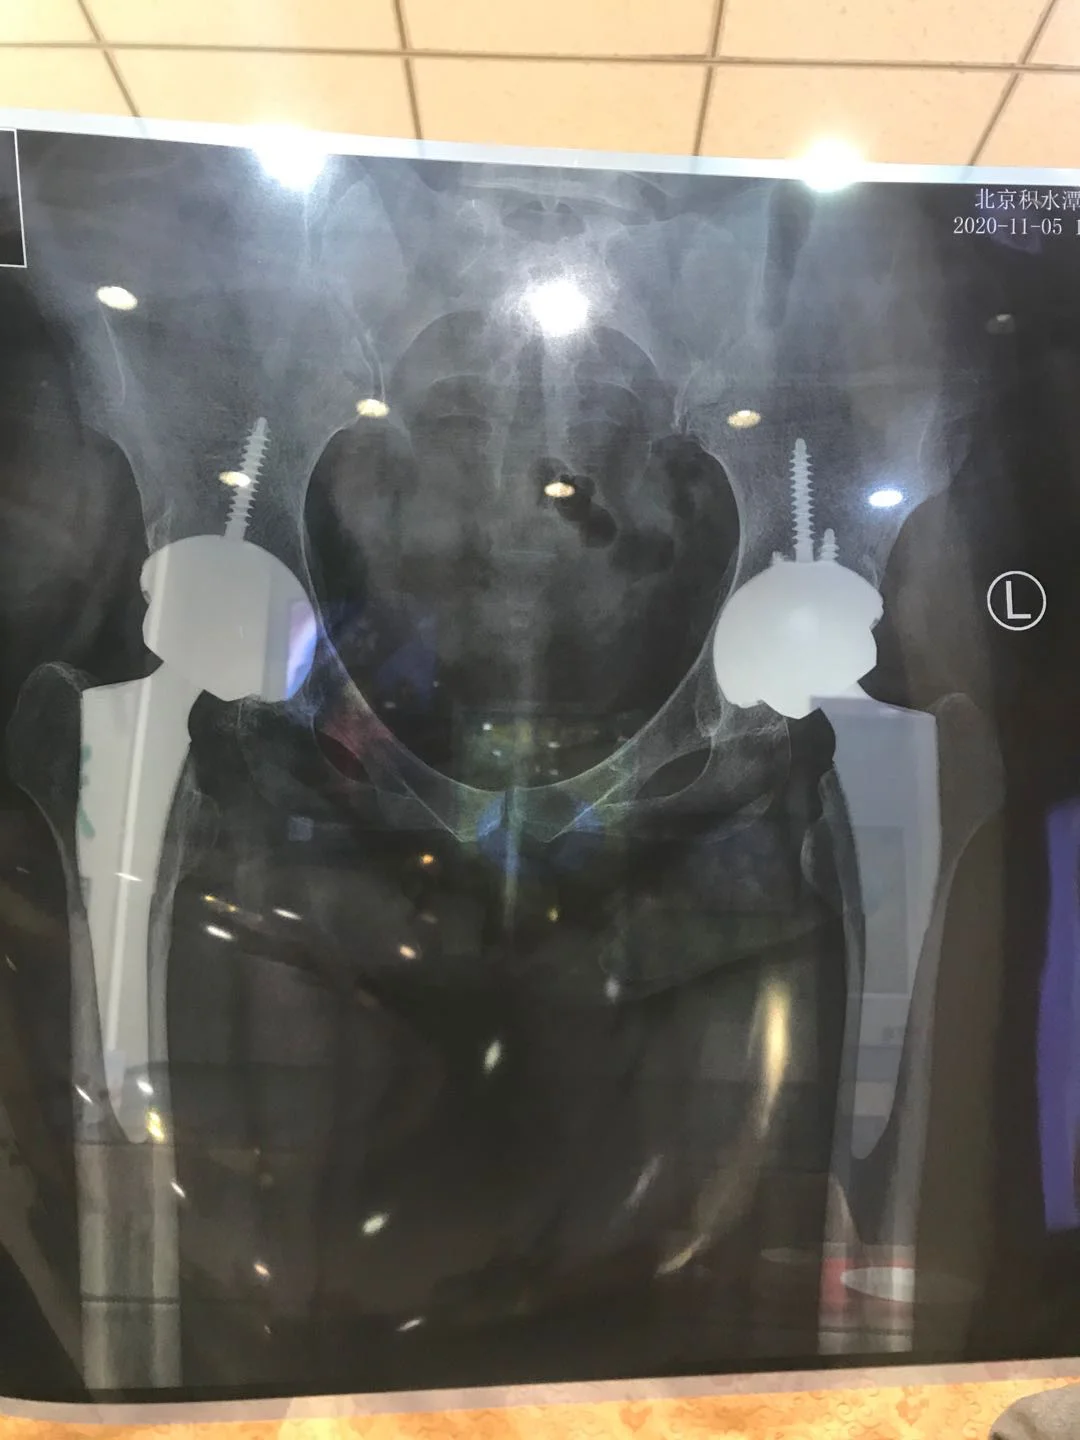

积水潭医院有三种不同股骨头和髋臼内衬材料-

?一是超高交联聚乙烯内衬对金属股骨头。

?二是超高交联聚乙烯内衬对陶瓷股骨头。

?三是陶瓷内衬对陶瓷股骨头。

三者之间每种材料都差距大约在一至两万左右。其中陶瓷对陶瓷是四代进口的粉陶。国产假体的陶瓷部分也是进口的。相同材质的国产关节目前与进口关节价格大约相差一至两万左右。金属股骨头对普通聚乙烯内衬组合现在使用较少,包括金属股骨头对超高交联聚乙烯内衬现在也很少用。原因是金属股骨头对普通聚乙烯内衬组合以及金属股骨头对超高交联聚乙烯内衬组合在使用的过程中耐磨性不如陶瓷对陶瓷组合,磨擦所产生的微粒人体不能吸收,继而容易导致假体周围骨溶解,假体产生松动下沉。

原理上说第一种可使用二十年以上,适合没有重体力的老年人,价格在三万以下。

第二种可使用二十五年和三十年以上,适合中老年纪人和没有体力劳动的人,价格在四至五万左右元。

第三种可用四十年以上或者是更长,适合年轻人和有体力劳动的人及有经济条件的老年人。价格在六万多元。所说的价格是假体的价格,不包括手术及其它费用。